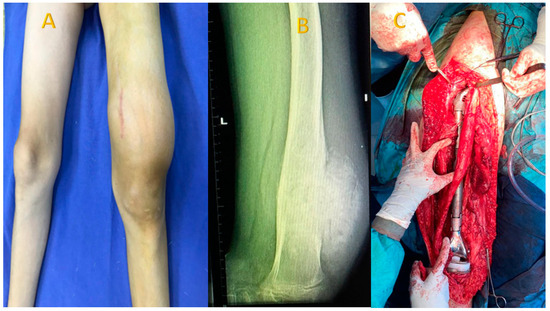

For the studied group, the main symptoms at presentation were attributed by the patient and relatives to trauma. The main symptoms were pain (93.8%), functional impotence (87.7%) and swelling (100%). Figure 2, Figure 3 and Figure 4 present the clinical, imaging and intra-operative appearance of the humeral and femoral OS for two of our patients.

Figure 2. Humeral osteosarcoma, 16-year-old male patient, 14 cm diameter tumour; (A) clinical aspect showing proximal humeral tumour, with a central scar—the site of the biopsy; (B) humeral X-ray showing periosteal destruction, infiltration in adjacent tissues and bone apposition; (C) CT scan demonstrating the rich vascularisation of the tumour; (D) MRI image with central tumour necrosis.